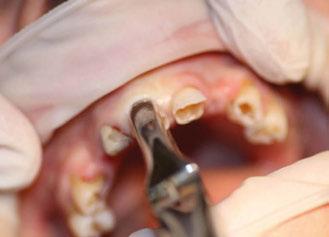

Ejecución técnica quirúrgica mediante férula guiada Bajo anestesia infiltrativa realizamos extracciones atraumáticas de todas las piezas a excepción de los dientes que actúan como anclaje o pilares para la fijación de la férula quirúrgica (Figuras 20 y 21). Seguidamente insertamos la férula comprobando una buena adaptabilidad y estabilidad

(Figuras 22 y 23). Se realiza fresado transgingival mínimamente invasivo y guiado hasta la inserción de los implantes, siguiendo el protocolo preestablecido e indicado (Figuras 24 a 26).

Durante la colocación de los implantes comprobamos una inserción con torque superior a 35 N/cm2

Retiramos la férula y comprobamos una correcta estabilidad primaria mediante mediación de valores

ISQ favorables en la mayoría de los implantes. Seguidamente se extraen los dientes remanentes que han actuado de medio retentivo para la férula quirúrgica.